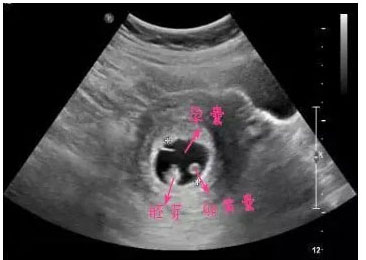

怀孕早期的B超检查主要是为了排除异位妊娠和异常妊娠,确定宝宝在妈妈的子宫里安全存活了。这时候的B超单上主要会出现妊娠囊(孕囊)、卵黄囊、胚芽、胎心这些指标。

正常情况下,如果子宫内出现孕囊,孕囊里有卵黄囊、胎芽及胎心,就基本可以确定宝宝安全了。如果没有观测到其中的某些指标也不要过于担心。可能是你太心急了,一般怀孕5~6周可以看孕囊,6~7周的时候可以看到胚芽胎心。